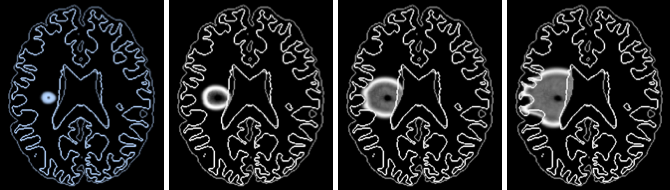

Gliome - reproduction d'une croissance exponentielle